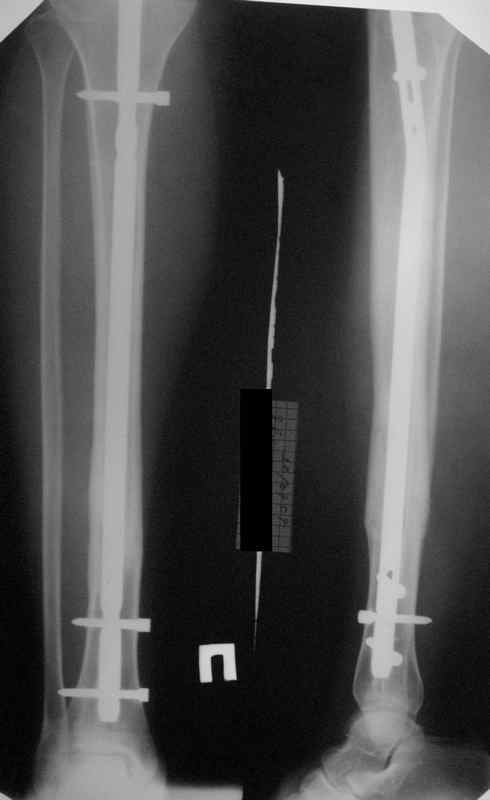

КА> Но почему решение динамизировать на сроке 8 недель с полным

В приложении картинка пациента со сломанным внизу гвоздем. Начал лечение в другом учреждении. Еще и адвокат к тому же.

Динамизировали через 8 недель, а оно поползло больше, чем хотелось бы.